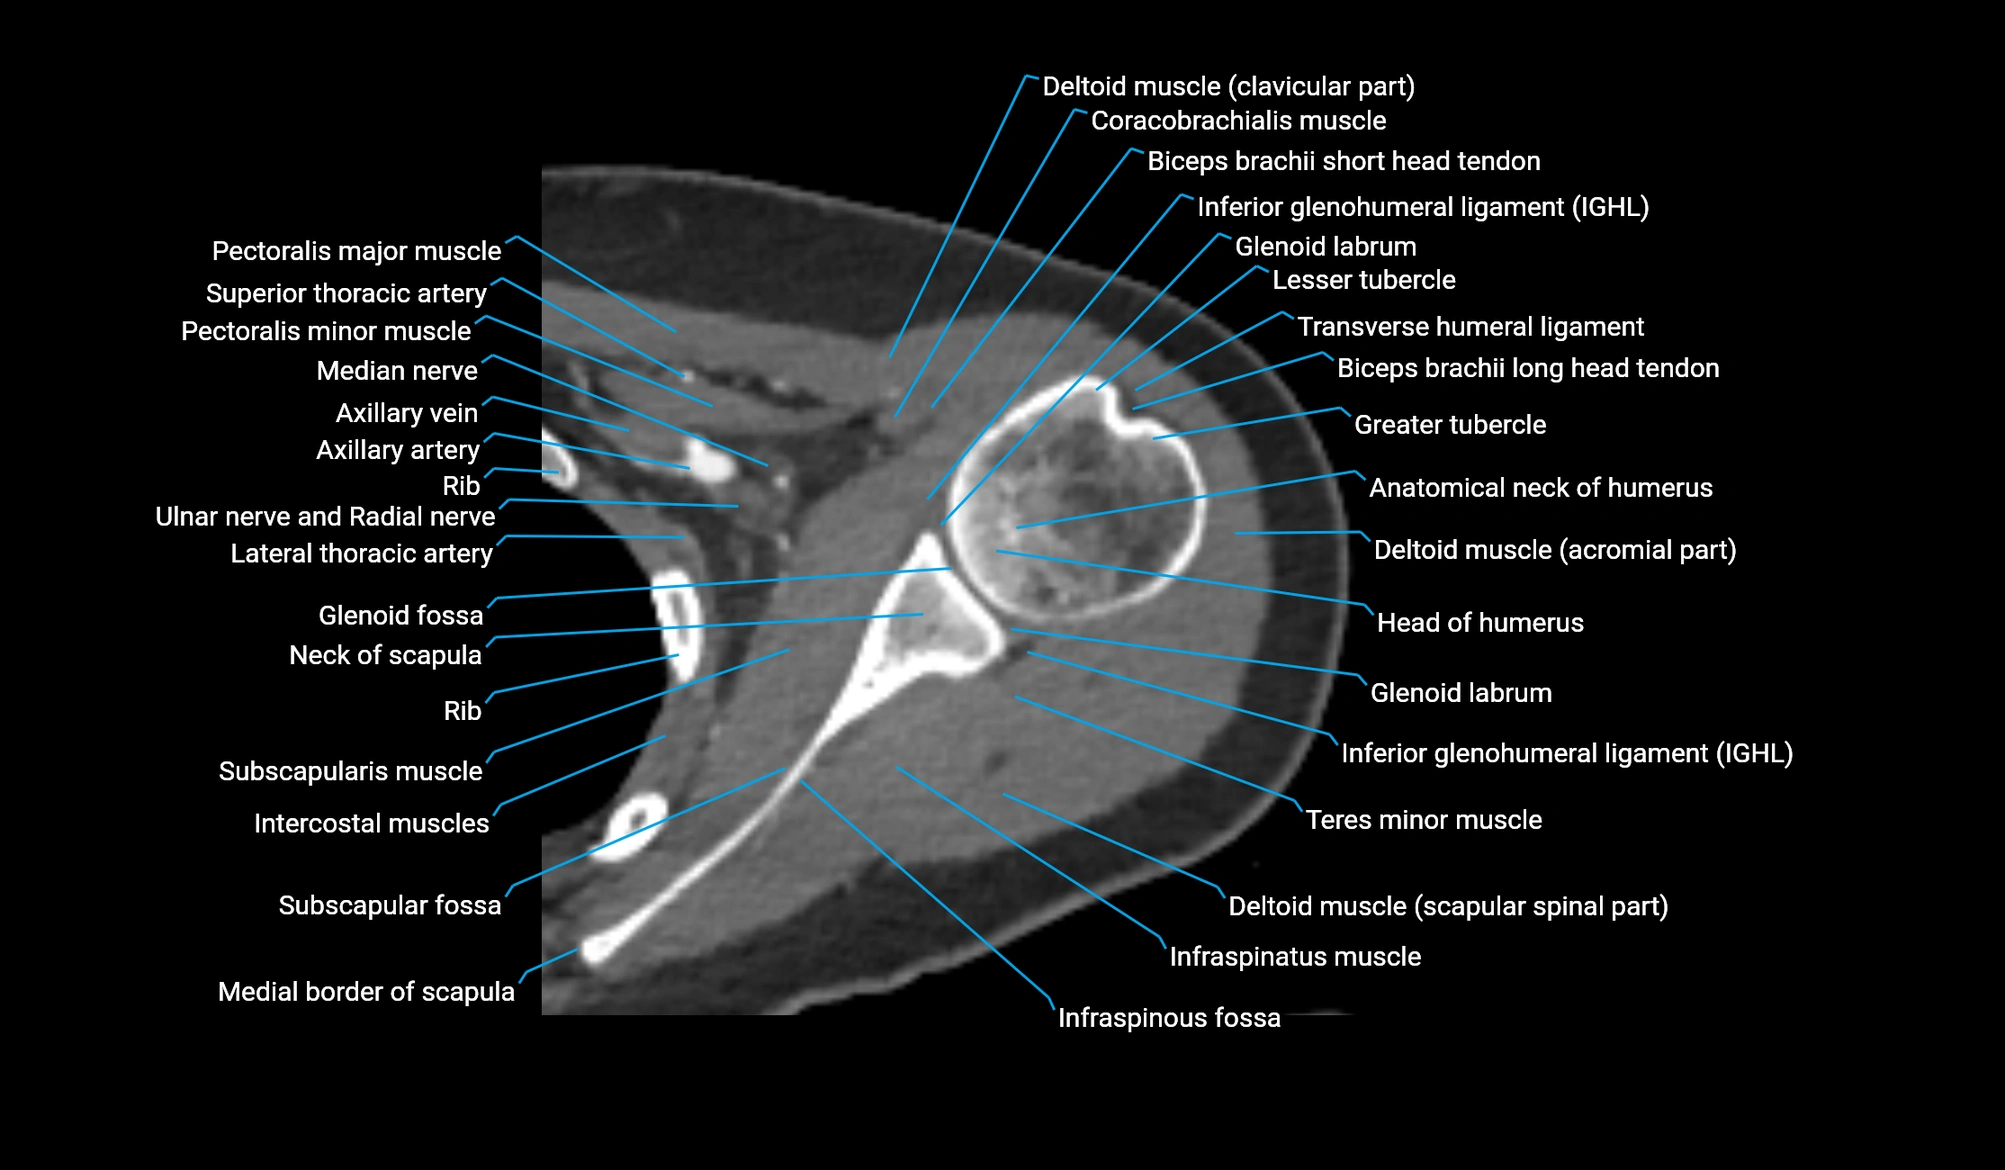

- Anatomical neck of humerus

- Glenohumeral joint capsule

- Glenohumeral ligaments

- Glenoid labrum

- Greater tubercle of humerus

- Head of humerus

- Inferior acromioclavicular ligament

- Inferior glenohumeral ligament

- Infraspinatus muscle

- Lesser tubercle of humerus

- Pectoralis major muscle

- Pectoralis minor muscle

- Subscapularis muscle

- Teres minor muscle